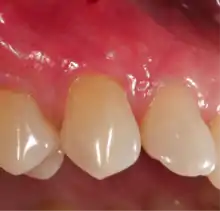

A small amount of blood (10 millilitres (0.35 imp fl oz; 0.34 US fl oz) per tube) is harvested and spun in a centrifuge for eight minutes at 1300 rpm. A fibrin clot packed with blood-derived growth factors, extra cellular matrix and hematopoietic stem cells is fabricated and implanted into the gums above the area of gum recession. Advanced platelet-rich fibrin will promote the patient's own gums to fabricate more gum thus eliminating the need to harvest gums from the roof of the mouth or the use of allografting tissue.

Following this procedure, patients have an improved quality of recovery and require less recovery time due to enhanced healing factors.[16][17][18][19]

A free gingival graft is a dental procedure where a small layer of tissue is removed from the palate of the patient's mouth and then relocated to the site of gum recession. It is sutured (stitched) into place and will serve to protect the exposed root as living tissue. The donor site will heal over a period of time without damage. This procedure is often used to increase the thickness of very thin gum tissue.

A subepithelial connective tissue graft takes tissue from under healthy gum tissue in the palate, which may be placed at the area of gum recession. This procedure has the advantage of excellent predictability of root coverage,[20] as well as decreased pain at the palatal donor site compared to the free gingival graft. The subepithelial connective tissue graft is a very common procedure for covering exposed roots.